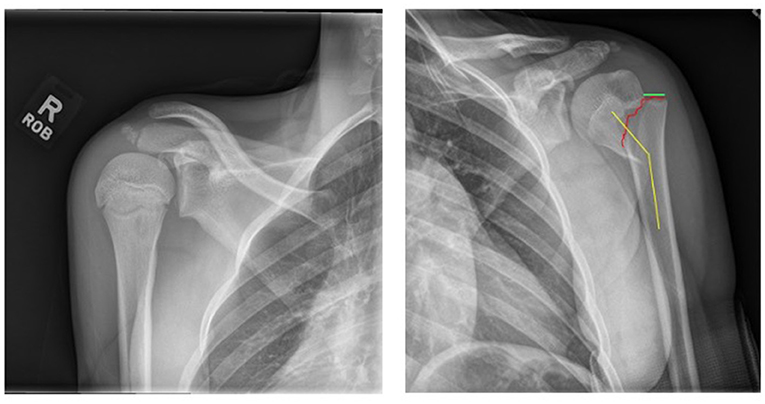

Humerus er den lange knogle, der udgør den øverste del af armen. Et brud eller en fraktur af humerus kan forekomme hvor som helst fra den del, der forbinder skulderen, ned til den del, der forbinder albuen. Når en fraktur opstår nær skulderen, kaldes det en proximal humerus fraktur. Proximale humerusfrakturer udgør ca. 3 % af alle frakturer hos børn [1]. Proximale humerusfrakturer kan opstå under aktiviteter som ridning, skiløb, snowboarding, trampolinspring eller ved trafikulykker [2].(Figur 1). Vores undersøgelse fokuserede specifikt på alvorlige brud, der var forskudt mere end halvdelen af knoglens bredde og vinklet mere end 30 grader.

Børns knogler har specielle dele, der kaldes vækstplader (Vækstplader er knogleområder, der er ansvarlige for at hjælpe knoglerne med at vokse bredere og længere, når børn bliver ældre. Vækstplader spiller også en vigtig rolle i reparation af brækkede knogler. Vækstplader bliver til et modent stykke knogle, når puberteten slutter, men børn har en særlig evne til at helbrede og vokse deres knogler, mens deres vækstplader er åbne. Op til 80 % af væksten i overarmen kommer fra den meget kraftige proximale humerus-vækstplade, hvilket har fået nogle læger til at tro, at brud i dette område kan helbrede og rette sig selv uden kirurgi – bedre end nogle brud i andre dele af kroppen [3].